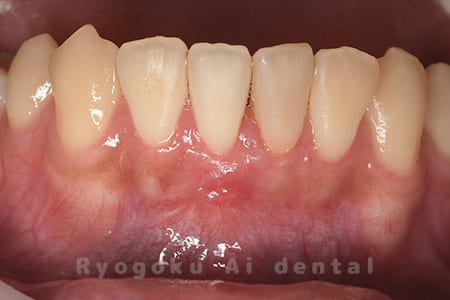

下の前歯の違和感が取れない、響く感じも強いとのことでご来院された患者様です。歯根端切除術を行い、術後の経過も良好です。

<リスク・副作用>

外科手術のため、術後に出血、痛みや腫れ、違和感を伴います。口腔内の状態によっては適応できないことがあります。歯根端切除で治らなければ抜歯を検討しなくていけない場合もあります。